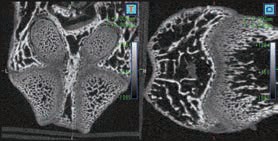

CosmoScan GX IIIは特に高い空間分解能を持ち、5µmまでの解像度と2.9µmのピクセルサイズ(FOV:8mm)を誇ります。これにより小さい骨の細かな解剖学的構造を含むex vivoサンプルの高品質な画像が得られます。

- 空間分解能 = 5µm 最小ピクセルサイズ = 2.9µm

Analyze 14.0ソフトウェアを用いることで、骨、体組成、脂肪量などのより高度な解析が可能になります。

- 解剖領域を高精度かつ迅速にセグメンテーション

- 長さ・体積・強度測定による詳細な統計解析

- 骨微細構造解析(BMA)機能(オプション)